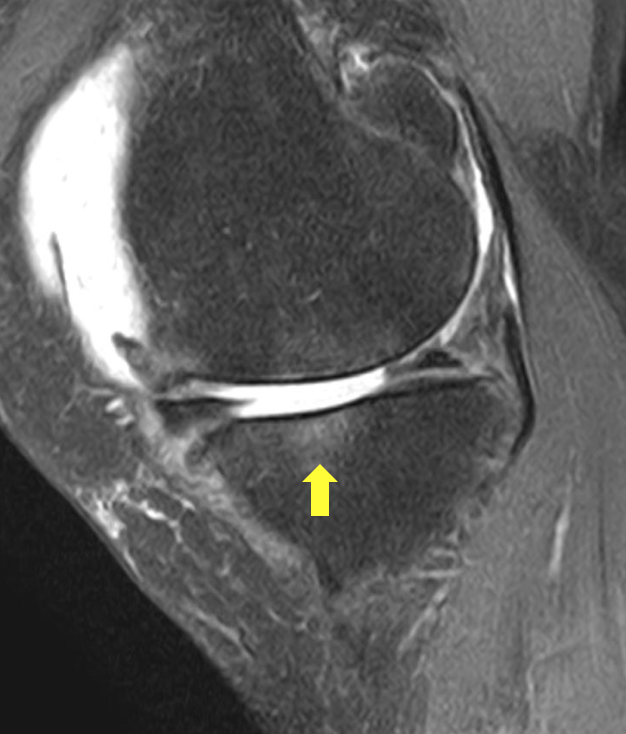

MRI撮影を行い、膝の脛骨にBMLを認めました。

そのため体外衝撃波治療を実施しました。

黄色矢印のところが白くなっています。

これがBMLです。

正面から見た画像とちょうど同じ部分に

BMLを認めています。